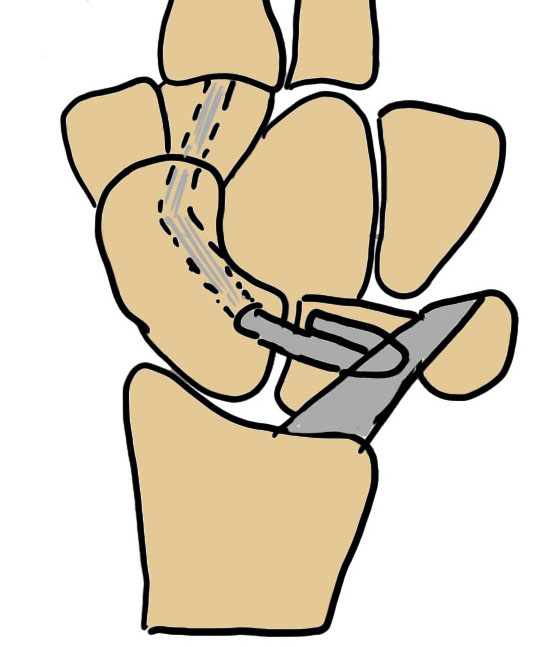

Tenodesis

Brunelli - replaces scaphotrapezial ligament, attaches to distal radius

Modified Brunelli - passes under / through radiotriquetral liagment, suture to itself

Three-ligament tenodesis - replaces scapotrapezial / scapholunate / radiotriquetral

| Brunelli Wrist Tenodesis | Modified Brunelli | Garcia-Elias Three-ligament tenodesis |

|---|---|---|

|

Dorsal approach - T capsulotomy or Berger - reduce SL joint with K wires - K wire SL joint and SC joint

Second volar approach - harvest half FCR, 8 cm long - leave attached distally

Drill hole in scaphoid tuberosity - pass volar to dorsal - insert dorsally to the distal radius |

Second volar approach - harvest half FCR, 8 cm long - leave attached distally Drill hole in scaphoid tuberosity - aim to exit close to SL joint - pass volar to dorsal

Pass under radiotriquetral liagment Suture to carpus / itself |

Dorsal approach - T capsulotomy or Berger - reduce SL joint and K wire - K wire SL joint and SC joint

Drill hole in scaphoid tuberosity - aim to exit close to SL joint - pass volar to dorsal

Anchor to lunate

Pass through radiotriquetral ligament

Suture to carpus / itself